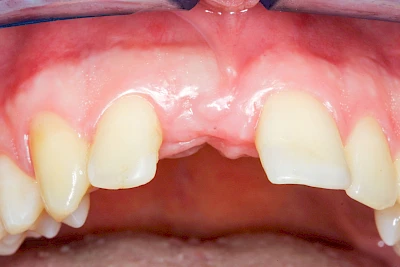

Implantate: Kronen & Brücken

Fehlen einzelne Zähne und die Nachbarzähne sind unbeschadet oder gut zahnärztlich versorgt, werden immer häufiger Implantate gewählt, um die Lücken zu schließen. Auch bei größeren oder verteilten Lücken, wenn keine herausnehmbare Prothese gewünscht ist, werden Implantate für Kronen- bzw. Brückenversorgungen gesetzt. In Einzelfällen entscheiden sich sogar zahnlose Patienten für eine festsitzende Versorgung auf Implantaten.

Varianten zur Verankerung von festsitzendem Zahnersatz auf Implantaten